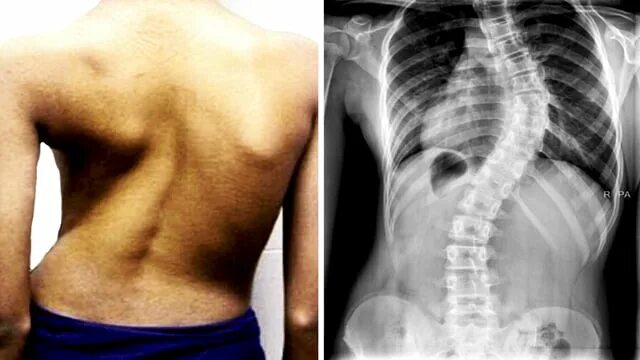

Горбы несущие